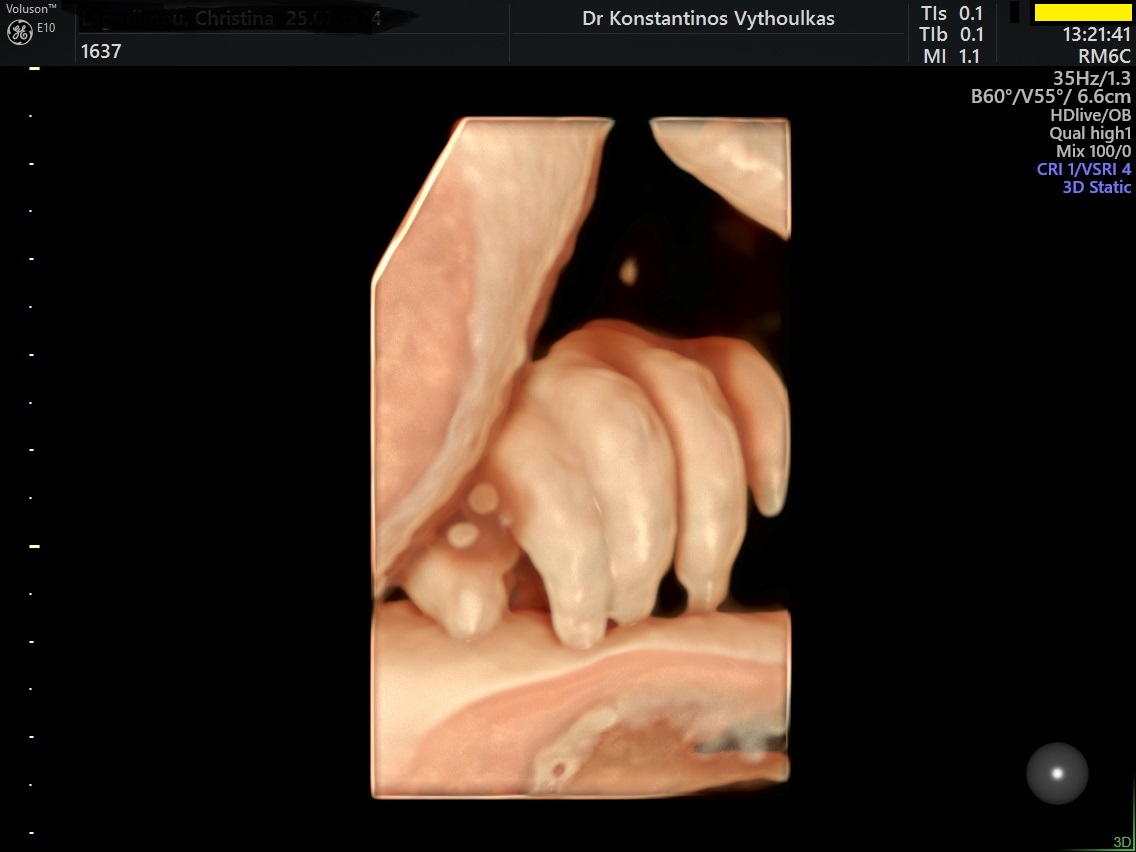

Φωτογραφίες από το αρχείο και από το χώρο του ιατρείου του γυναικολόγου Βυθούλκα Κωνσταντίνου, καθώς και του εργαστηρίου της κυτταρολόγου Λιβέρη Κατερίνας.